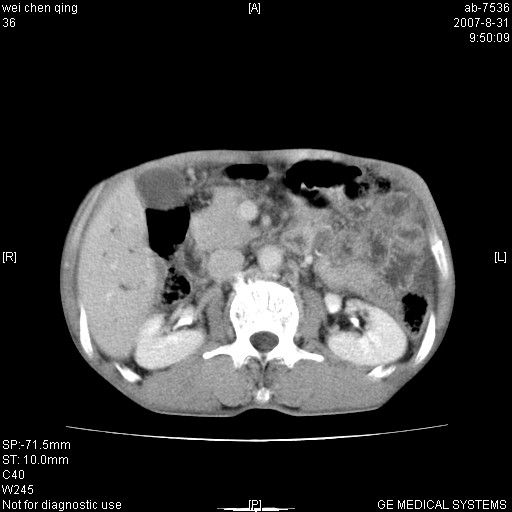

以下是引用zyyzzy在2007-8-31 14:34:00的发言:[br]该病人肝内胆管扩张,胆囊及胆总管未见明显扩张。在倒数第9层图像上可看到左右肝管结合部(肝总管)有软组织影,此处应薄层扫描。考虑肝总管占位(ca)、腹水。[br]